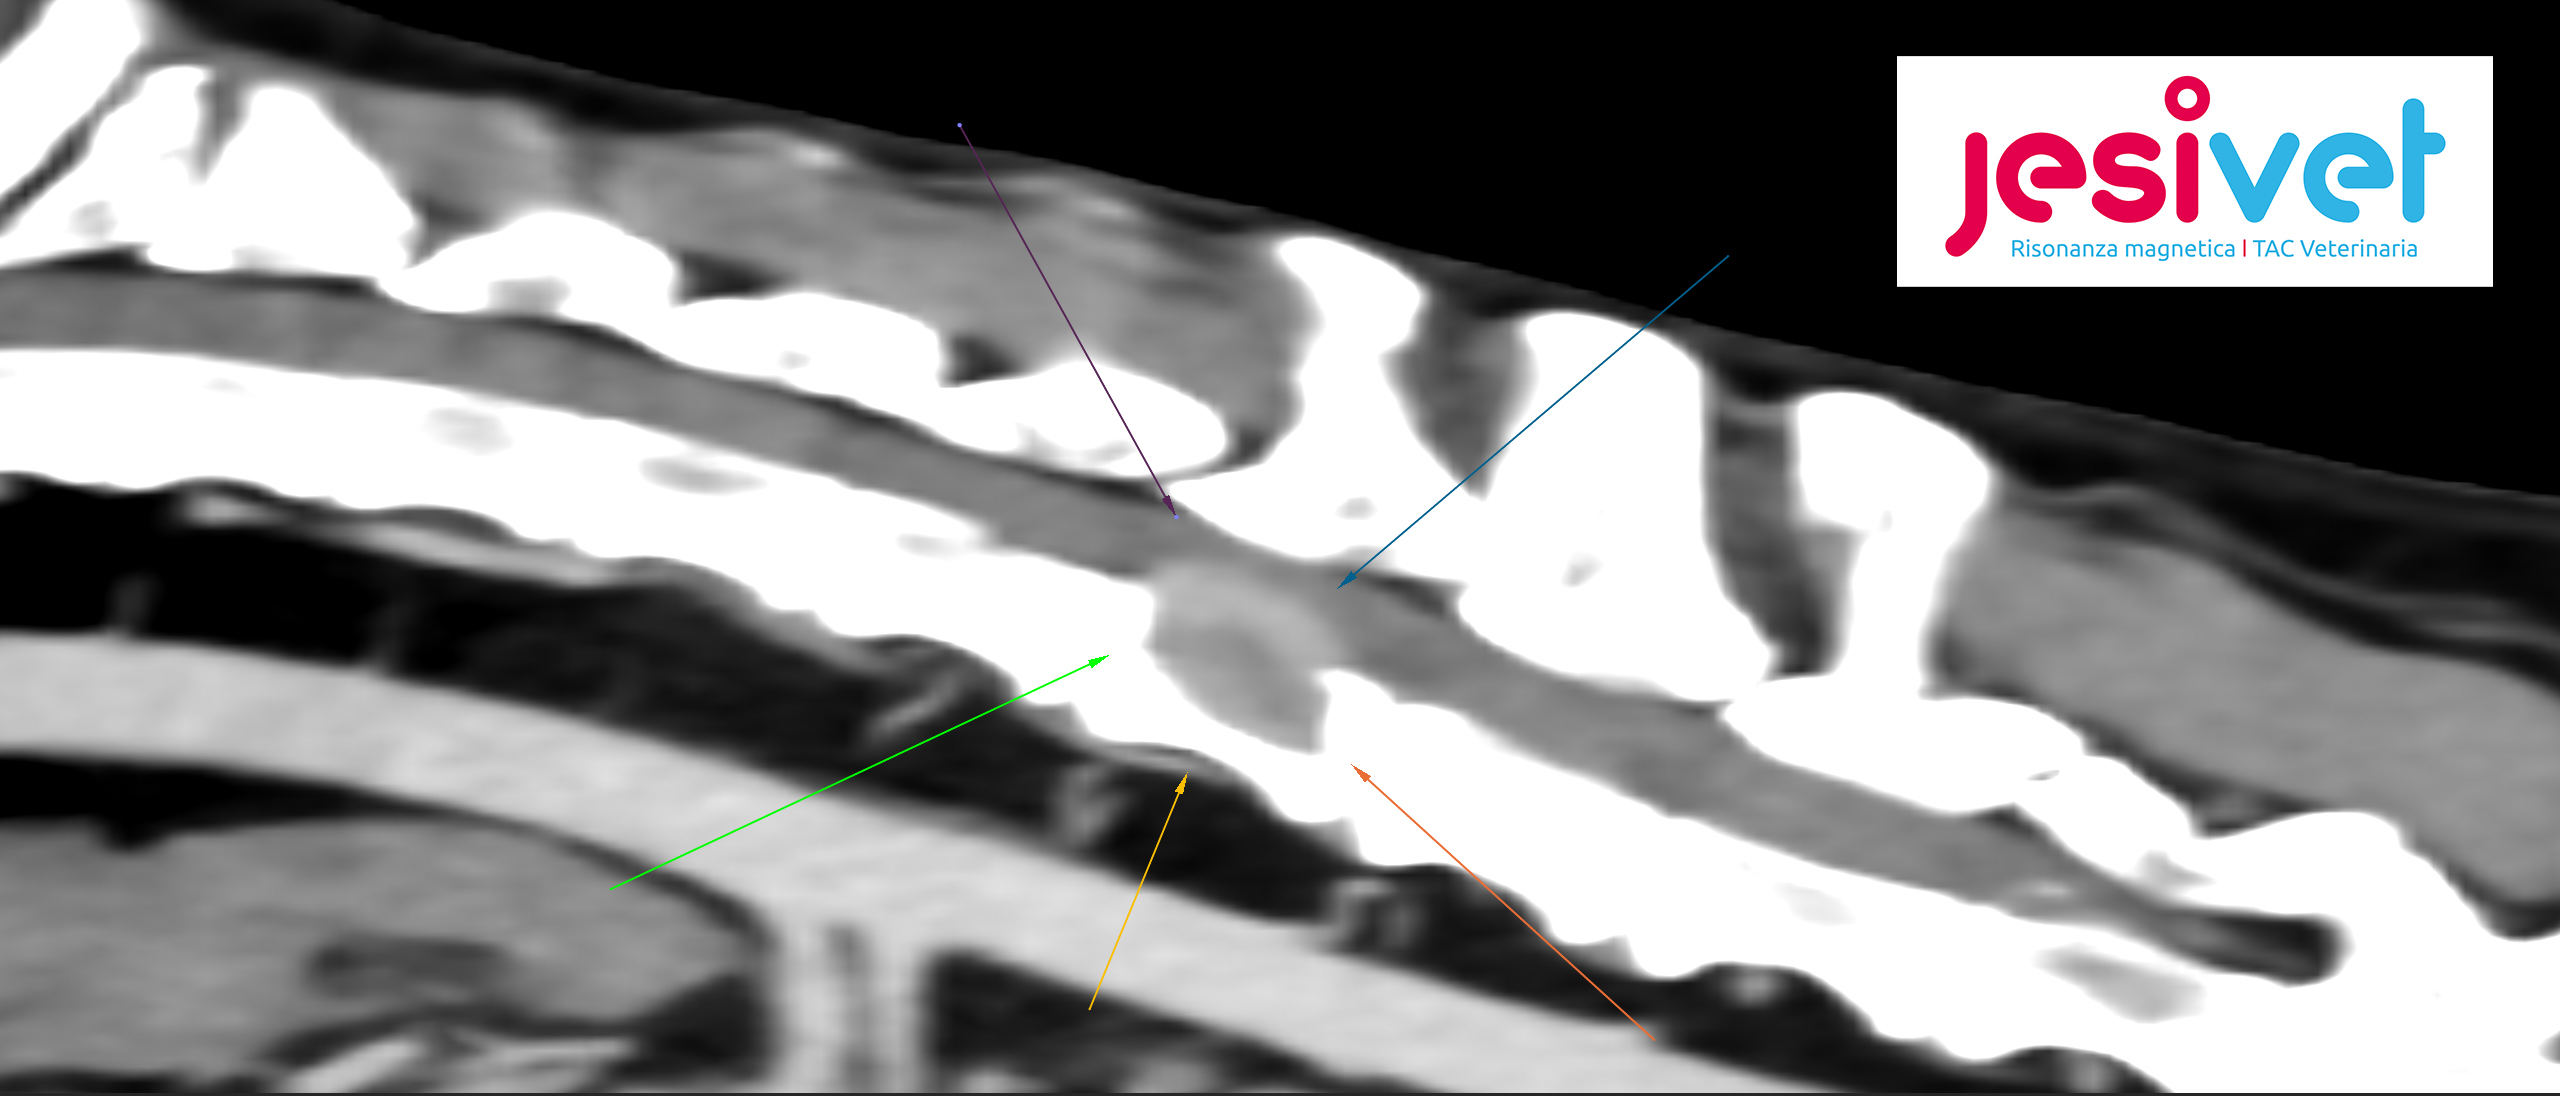

Mieloma Multiplo – Ad Aprile 2021 ci è stato riferito Artù per una paresi agli arti posteriori e forte dolore alla schiena che gli impedivano completamente di muoversi. Il quadro clinico era particolarmente complesso, per questo motivo si è deciso di procedere con un approfondimento con la nostra TAC a 16 strati della GE. Tramite questo esame diagnostico di secondo livello sono state evidenziate lesioni multiple ala colonna vertebrale e una massa più importate che comprimeva il midollo ed impediva la corretta propagazione dell’impulso nervoso agli arti posteriori.

La diagnosi finale è stata di Mieloma Multiplo, una rara neoplasia del midollo osseo. Sembrava davvero una storia che non potesse finire bene…ed invece…